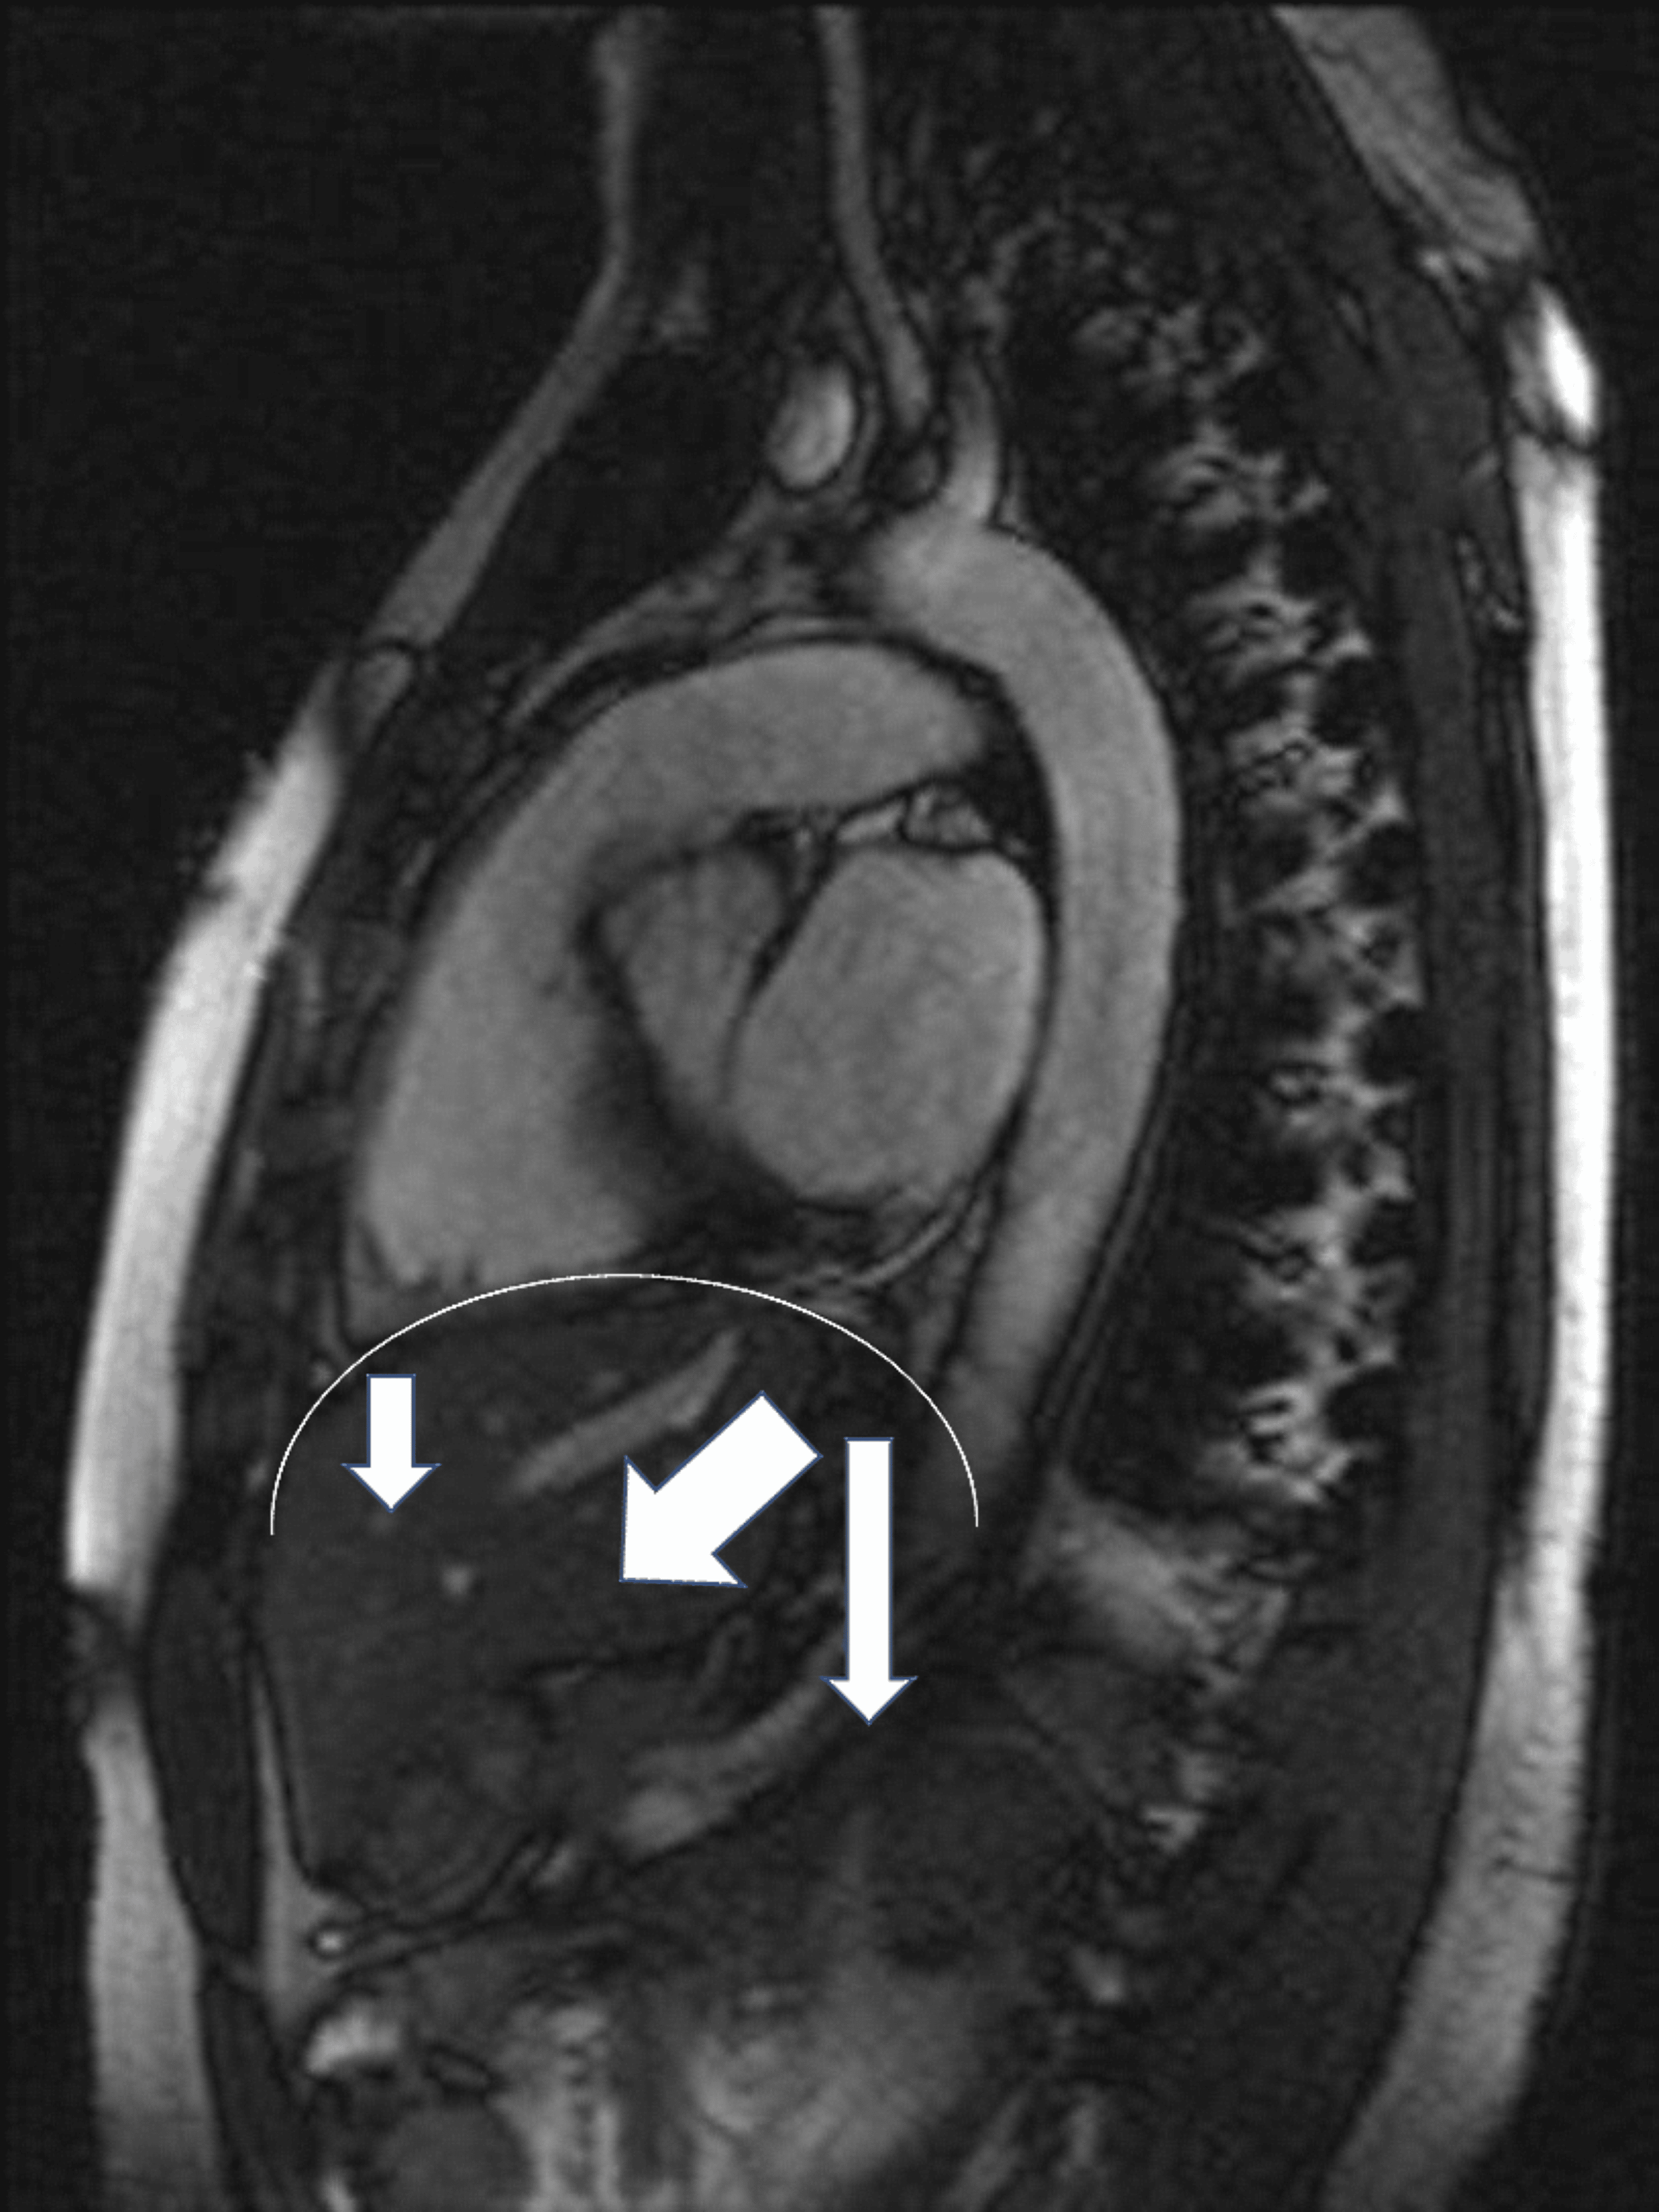

From www.nejm.org

Dysfunction of the Diaphragm NEJM Split Carb Diaphragm Symptoms The #1 air jet (air bleed, air bleeder etc.) is part of the carburetor like all carbs everywhere. Often, once the solvent eavporates, it will shrink bak. If you cleaned the diapghram in carb solvent, it well swell. It is a fixed orifice in the air horn of. Check for dirt, debris, or. If there is no vacuum pressure the. Split Carb Diaphragm Symptoms.